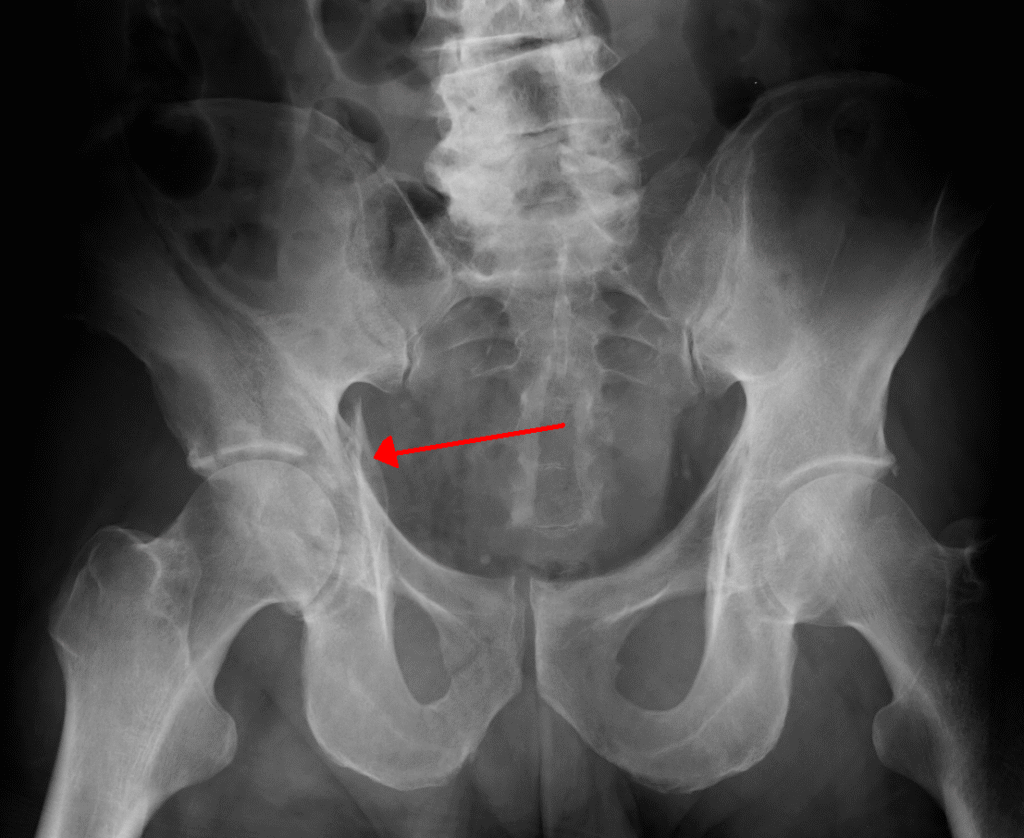

Datos clínicos y detección: La osteoporosis suele ser silenciosa hasta que ocurre una fractura. Las fracturas más características son: cadera, columna vertebral (fracturas vertebrales) y muñeca. Otros signos: pérdida de estatura progresiva y dolor dorsal por fracturas vertebrales. La densitometría ósea (DXA) es la prueba estándar para medir densidad mineral ósea y definir osteoporosis según criterios de la Organización Mundial de la Salud (T-score ≤ −2.5). Existen herramientas para la evaluación de riesgo para padecer osteoporosis (OST, Osteoporosis Self Assessment Tool) y para la evaluación del riesgo para padecer una fractura por osteoporosis (CAROC System), la cual integra densidad y factores clínicos para estimar el riesgo fracturario a 10 años.

Complicaciones: Las fracturas por fragilidad, especialmente la fractura de cadera, se asocian a morbimortalidad importante: dolor crónico, pérdida de autonomía, discapacidad, necesidad de cuidados a largo plazo y un aumento del riesgo de muerte en el primer año tras la fractura (la mortalidad un año después de una fractura de cadera puede superar el 20% en muchos contextos). Las fracturas vertebrales repetidas reducen la calidad de vida y capacidad respiratoria; además, una fractura por fragilidad aumenta el riesgo de nuevas fracturas.

Imagen por James Heilman, MD – Own work, CC BY-SA 3.0.